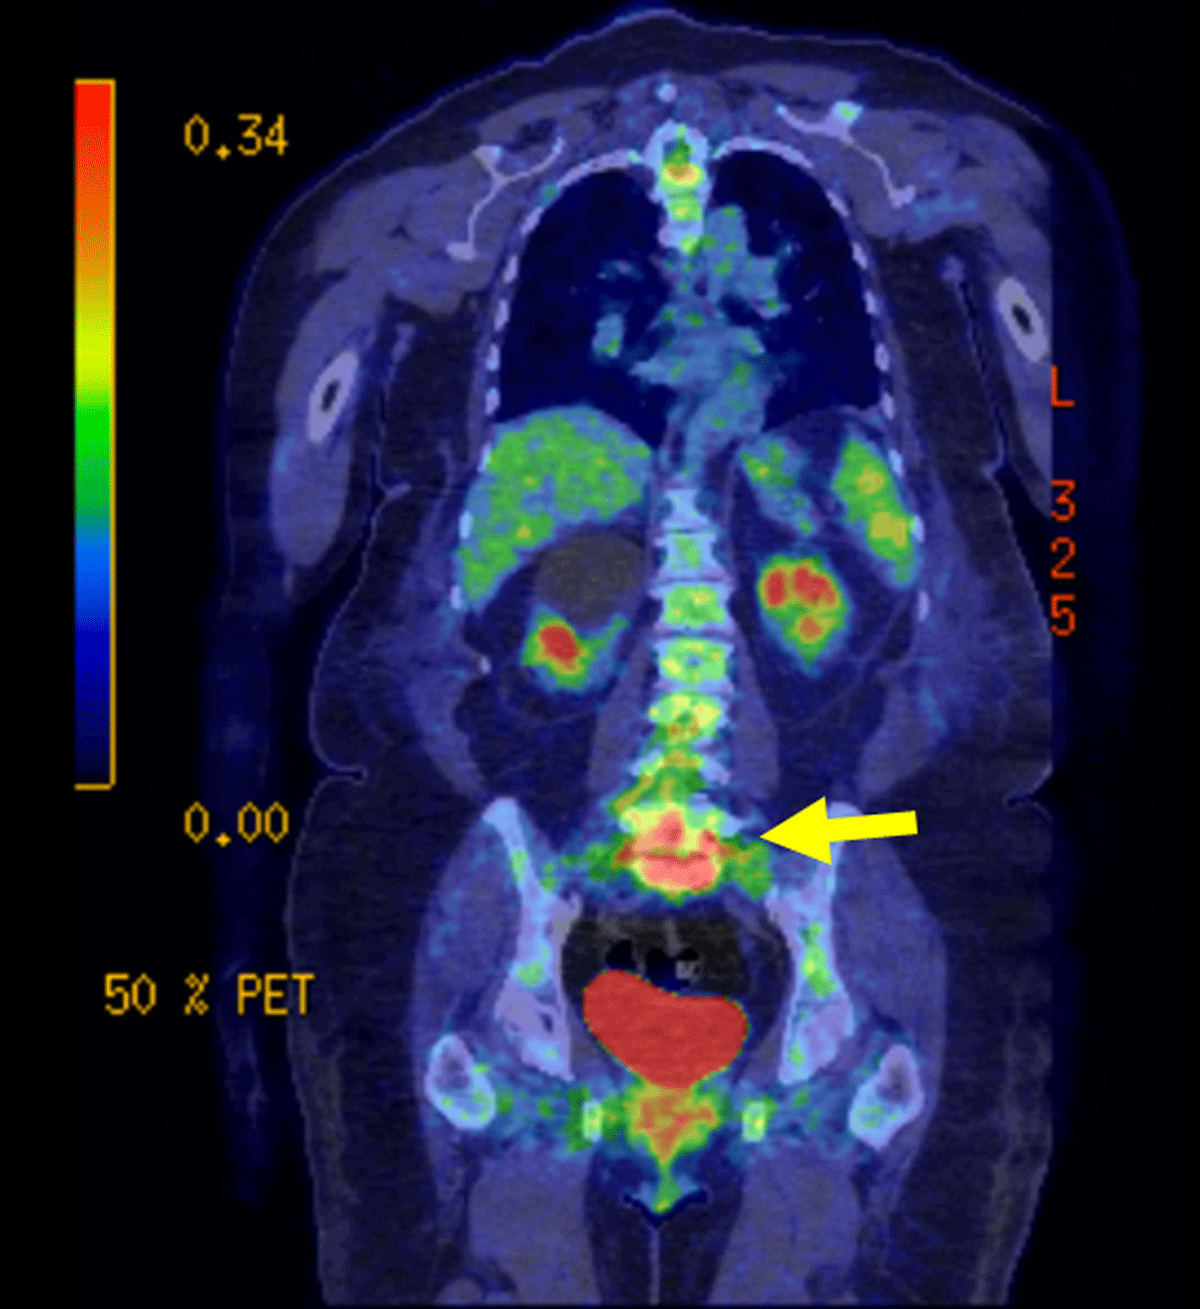

Figure 3

Coronal FDG PET-CT: PET-CT using F-FDG was performed in the context of a possible infection which revealed intense activity at the junction of L5-S1 and the surrounding tissue.